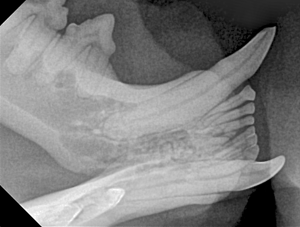

Feline Full Mouth Radiograph example